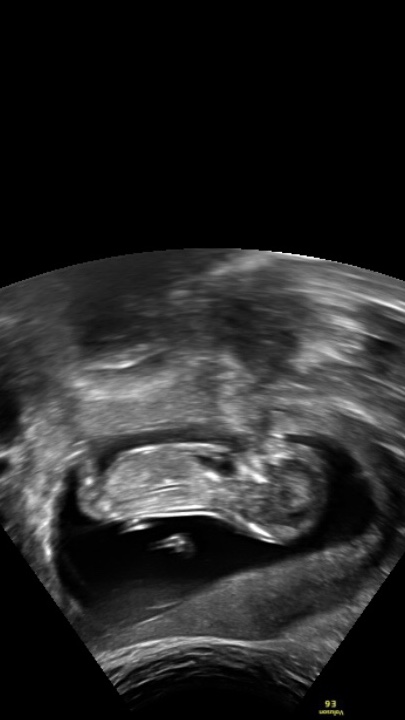

I’m driving myself mad looking for scan pictures similar to mine so I’m hoping somebody might have a guess for me on my scan pic and potty shot at 13 weeks! Baby was upside down so I’ve turned the pic around in hope it makes it easier to see!

Thanks so much! Attachment 39299